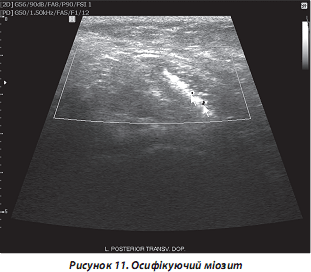

г) осифікуючий міозит локалізується найбільш часто в ліктьовій, тазостегновій, сідничній ділянках. За генезом у 60–75 % випадків він є посттравматичним, постінфарктним, ідіопатич- ним, нейрогенним. УЗД-ознаки — гіперехогенні структури в проекції м’язів, що скануються, з акустичною тінню (рис. 11).